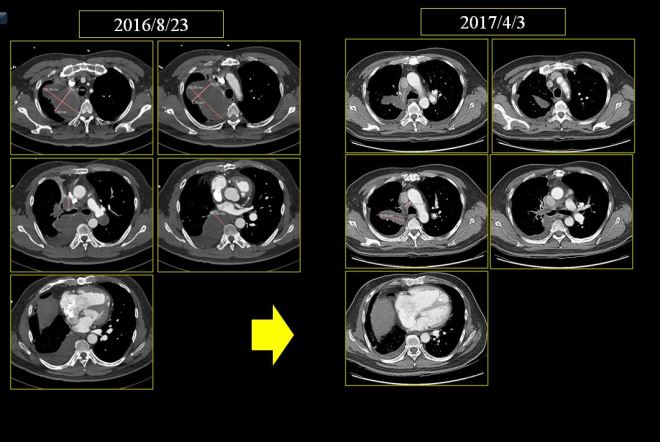

역시 결과는 좋아서 2016년 8월부터 2017년 4월까지 사이에 사진을 비교하면 현격한 변화가 있었다. 하지만 adiamycin은 6차 이상을 신독성으로 인하여서 시행하기가 어려운 항암제이므로 항암이 중단되었고 항암을 중단하는 사이에 초기 1월에서부터 4월까지는 좋아진 것도 있고 나빠진것도 있어서 소강 상태로 내원하게 되었다. 이 분은 매우 운이 좋은 분이다. 만약 주치의가 CYVADIC의 항암 방법을 고집했더라면 AC 두 가지 약물을 사용해서 나온 이 같은 좋은 결과가 나오지 않았으리라고 생각한다.

본원 내원 이후 보호자들의 근심스러운 얼굴에도 불구하고 환자의 상태는 좋아져서 chest와 CT 상의 변화를 보이게 되었다. 2017년 5월 18일 아산병원에서 가져온 CT를 본원에서 비교하였다. 환자 보호자는 주치의 선생이 달라진 게 없다고 하였다는 한마디를 하며 줄었다는 나의 이야기를 미심쩍어 하였다.

다음은 이 환자의 초기 2017년 4월 3일 CT와 이후 내원하여 4월 17일부터 한약 복용하고 한 달 뒤인 5월 18일 사진, 그리고 치료 3달 뒤인 7월 18일 사진을 coronal view (세운 채로 쪼갠 사진으로 앞에서 뒤로 단면이 cut된 사진)를 제시해 보면 확연히 종양이 줄어드는 것을 알 수가 있다. 그리고 또한 pleural thickening도 많이 감소된 것을 보게 된다. 비록 아산 소견서는 별 변화 없는것처럼 들었다고 하였지만 이 같은 차이가 쉽게 얻어지는 것은 아니며, 한약 양약 환자와 보호자의 노력이 합쳐져서 얻어지는 것임을 명심해야 한다.

이 환자의 종양은 명확히 범주를 정하기에는 불규칙한 모양을 하고 있으나 대략 가장 크게 보이는 데를 기준으로 하여서 체적을 측정하면 (이는 전문가가 아닌 나의 측정이므로 오차가 꽤 있을 수는 있음을 양해를 구한다) 4월 3일 52CC 정도에서 한 달 치료 후에 35CC 정도로 감소되었고 또 7월 18일 마지막에는 18CC 정도로 줄었다고 볼 수 있다.